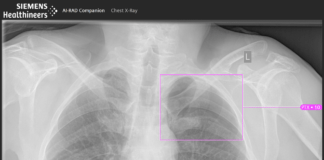

Siemens expands AI portfolio in the field of clinical decision-making

The AI-Rad Companion family supports radiologists, radiation oncologists, radiotherapists, and medical physicists through automated post-processing of MRI, CT, and X-ray datasets. The company claims...